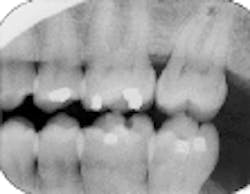

Overlap of contact surfaces

Perhaps the most common error is the overlapping of contacting surfaces (see Radiograph 1). When this occurs, the interpretation of caries is difficult at best. At worst, depending on the degree of overlap, interpretation often becomes virtually impossible.

The overlap is the result of incorrect horizontal angulation. With the paralleling technique, improper film-holder placement can be the cause. A simple adjustment in the film-holder`s position places it parallel to the facial surfaces of the teeth being exposed.

But the overlap can also be the result of errors in the angle of projection either mesiodistally or distomesially. When the horizontal plane projection is directed from mesial to distal, the resulting larger areas of overlap appear in the posterior portion of the film. Conversely, if the larger overlap appears in the anterior portion of the film, the horizontal plane of projection was directed distal to mesial.

To change this, place the film parallel to an imaginary line that is parallel to the facial surfaces of the teeth. The plane of the positioning indicating device/cone (PID) should then be parallel to this line and the film together. To determine the degree of overlap, use this general rule: If the overlap covers more than one-half of the enamel`s width, the degree of incipient decay and etchings are difficult to determine, and major technique problems need to be addressed.